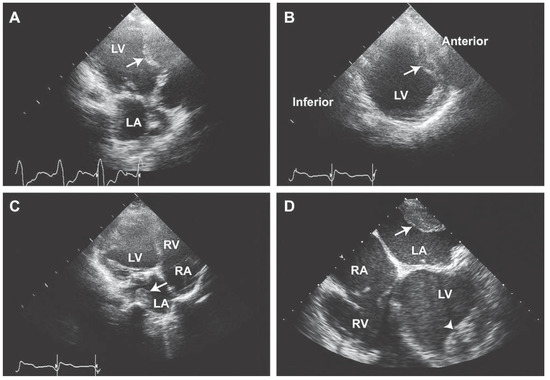

An Unusual Case of Multi-Chamber Thrombi in a Patient with Mitral Valve Repair

by Mohammad Q. Najib, Jhansi L. Ganji and Hari P. Chaliki

Cardiovasc. Med. 2013, 16(4), 131; https://doi.org/10.4414/cvm.2013.00119 (registering DOI) - 17 Apr 2013

A 55-year-old man with a history of non-ischaemic cardiomyopathy and implantation of a biventricular pacemaker with a defibrillator was referred for evaluation for a heart transplant because of New York Heart Association class IV heart failure symptoms[...] Full article

Figure 1